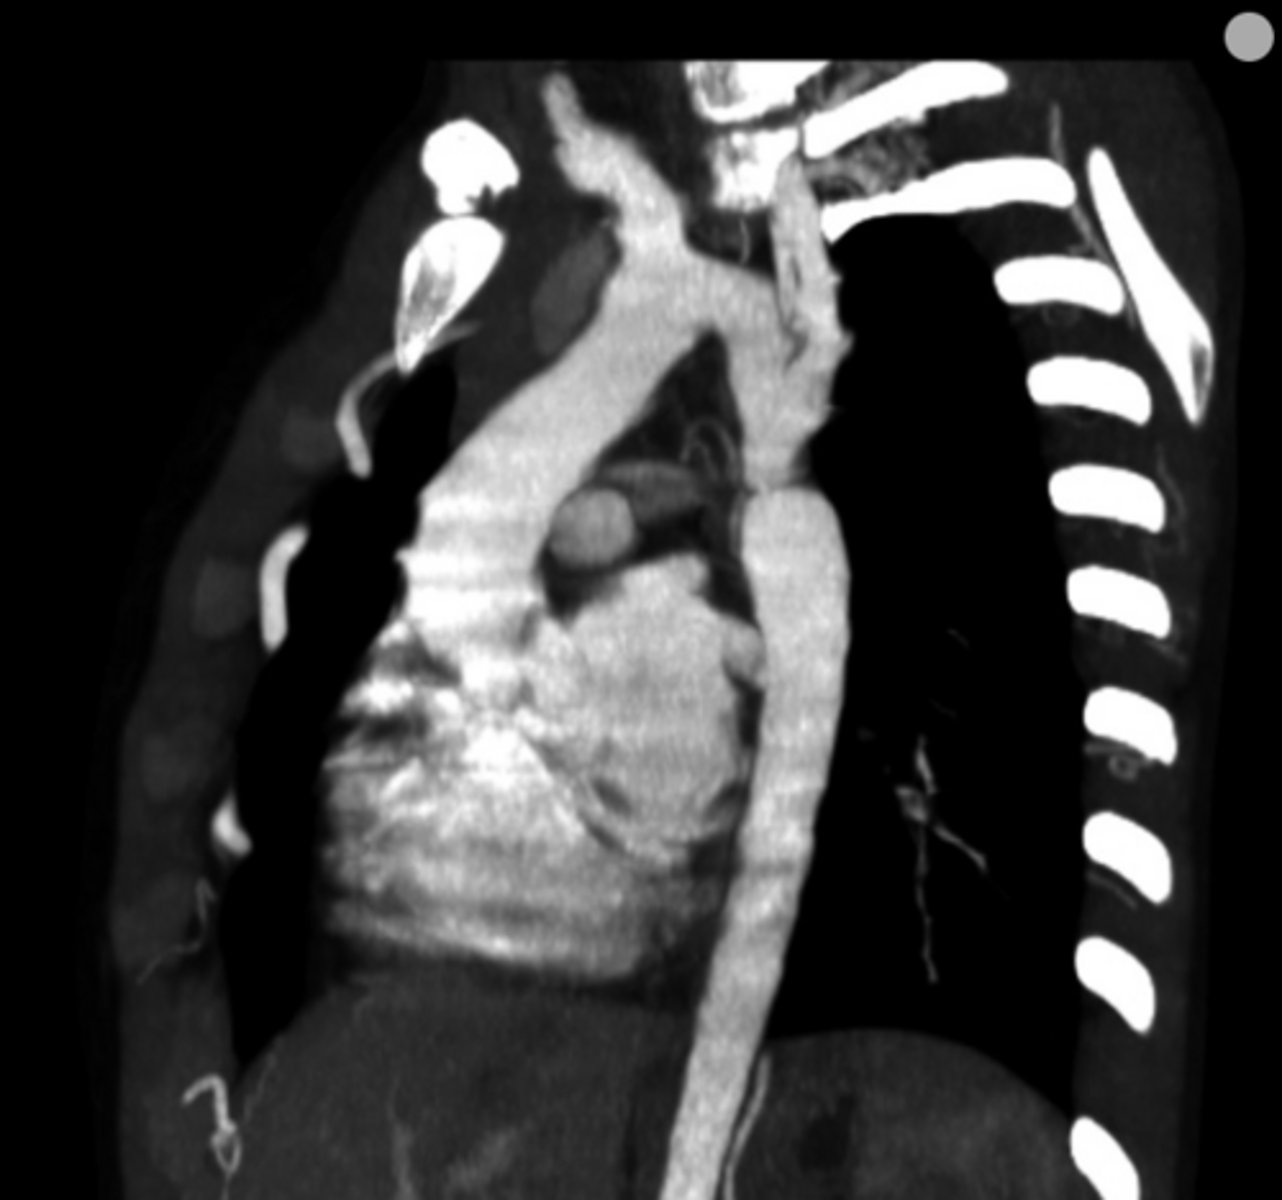

What is coarctation of the aorta?

Congenital narrowing of the aorta.

<p>Congenital narrowing of the aorta.</p>

79

New cards

What are the key features of infantile coarctation of the aorta?

Symptomatic in early childhood, tubular hypoplasia of the aortic arch, occurs proximal to a PDA.

<p>Symptomatic in early childhood, tubular hypoplasia of the aortic arch, occurs proximal to a PDA.</p>

80

What are the key features of adult coarctation of the aorta?

Narrowing opposite a closed ductus arteriosus, distal to the great vessels from the aortic arch.

<p>Narrowing opposite a closed ductus arteriosus, distal to the great vessels from the aortic arch.</p>

81